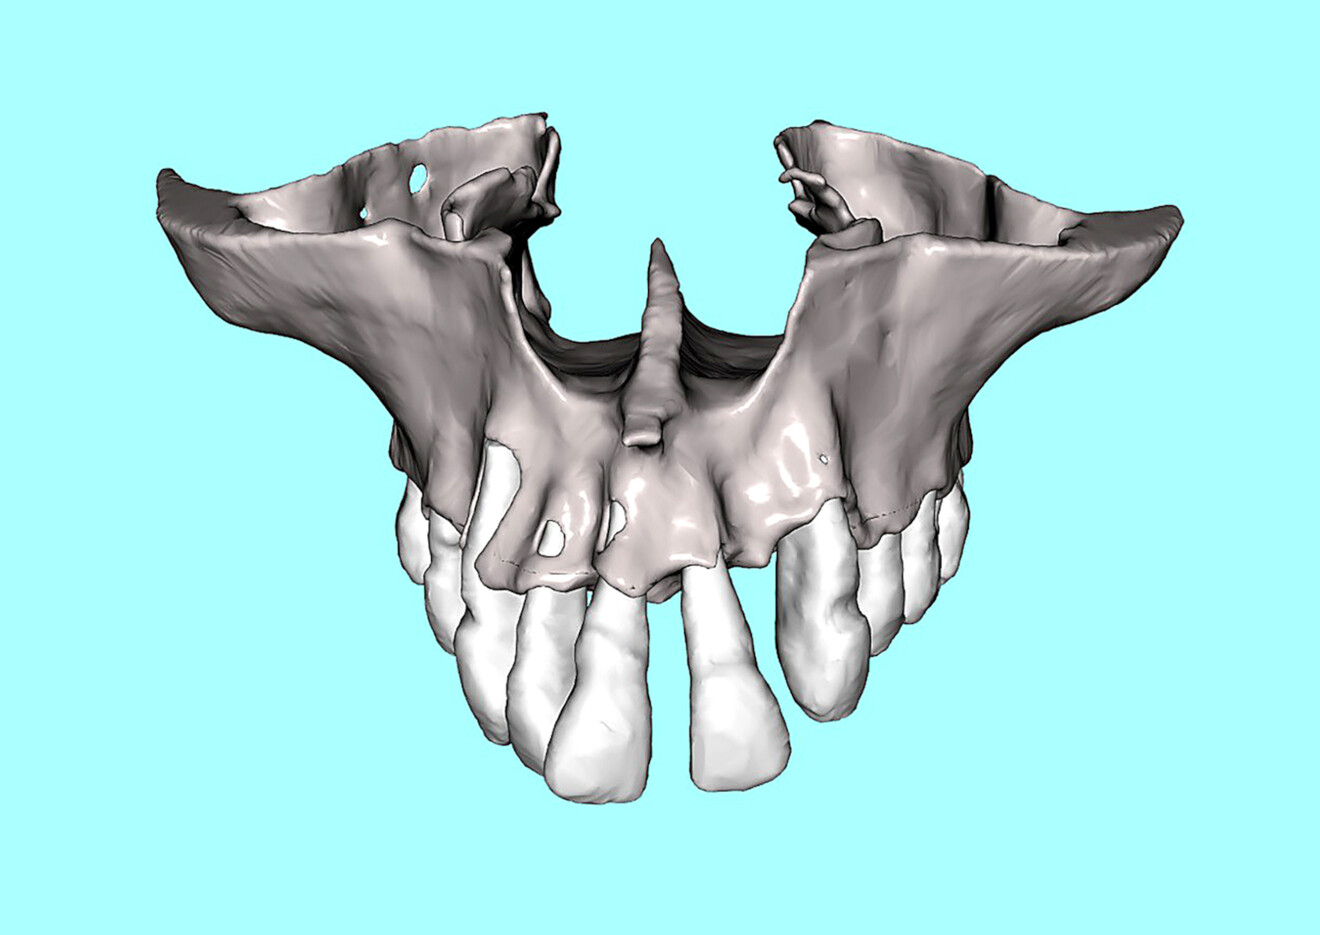

Advanced AI-driven bone and tooth segmentation was applied to the maxillary arch to aid in the final diagnosis and treatment plan for each potential implant receptor site (Fig. 4a). The spacing of the existing natural teeth and the full topography of the maxillary bone could be visualised, providing important information required for proper implant placement (Fig. 4b). The segmented natural teeth were virtually extracted so that the bone contours and socket defects could be readily assessed (Fig. 4c).

Fig. 4a: 3D volumetric reconstruction of the maxilla. Extent of the bone loss and spacing of the anterior teeth.